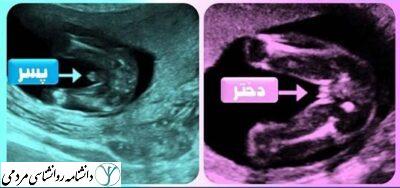

طی یکی دو ماه اول پس از انعقاد نطفه، تنها از کروموزومهای جنین میتوان فهمید که جنین دختر است یا پسر. تا این مرحله هر دو جنس ظاهرشان یکسان است: بافتهایی دارند که سرانجام تبدیل به بیضه یا تخمدان خواهد شد و زایدهای تناسلی که عاقبت به شکل آلت مردانه یا کلیتوریس زن درخواهد آمد. اما بین ماه دوم و سوم، غده جنسی ابتدایی در صورت نر بودن ساخت ژنتیکی جنین (داشتن کروموزومهای XY) تبدیل به بیضه، و اگر جنین مادینه باشد (کروموزومهای XX) تبدیل به تخمدان میشود. همینکه بیضهها یا تخمدان بهوجود بیایند هورمونهای جنسی تولید میکنند و این هورمونها رشد ساختارهای درونی تولید مثل و اندامهای جنسی بیرونی را کنترل میکنند. اهمیت هورمونهای جنسی در دوره رشد جنینی حتی از اهمیت آنها برای رشد ویژگیهای جنسی در دورهی بزرگسالی هم بیشتر است.